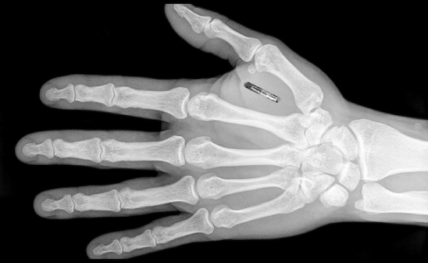

Чіп під шкірою замість паспорту. Фото https://psm7.com/

У Швеції розробили мікрочіп, який імплантують під шкіру та завантажують туди ковід-паспорт. Імплант, розміром з рисове зернятко, здатний зберігати не лише дані про вакцинацію, а інші важливі документи.

За словами керівника компанії Ханнеса Сджоблада, мікрочіп підшивають під шкіру між великим і вказівним пальцями, або трошки вище запʼястя за допомогою спеціального шприца. При цьому за бажання його можна без проблем вилучити в будь-який момент.

Чіп імплантують під шкіру на руці